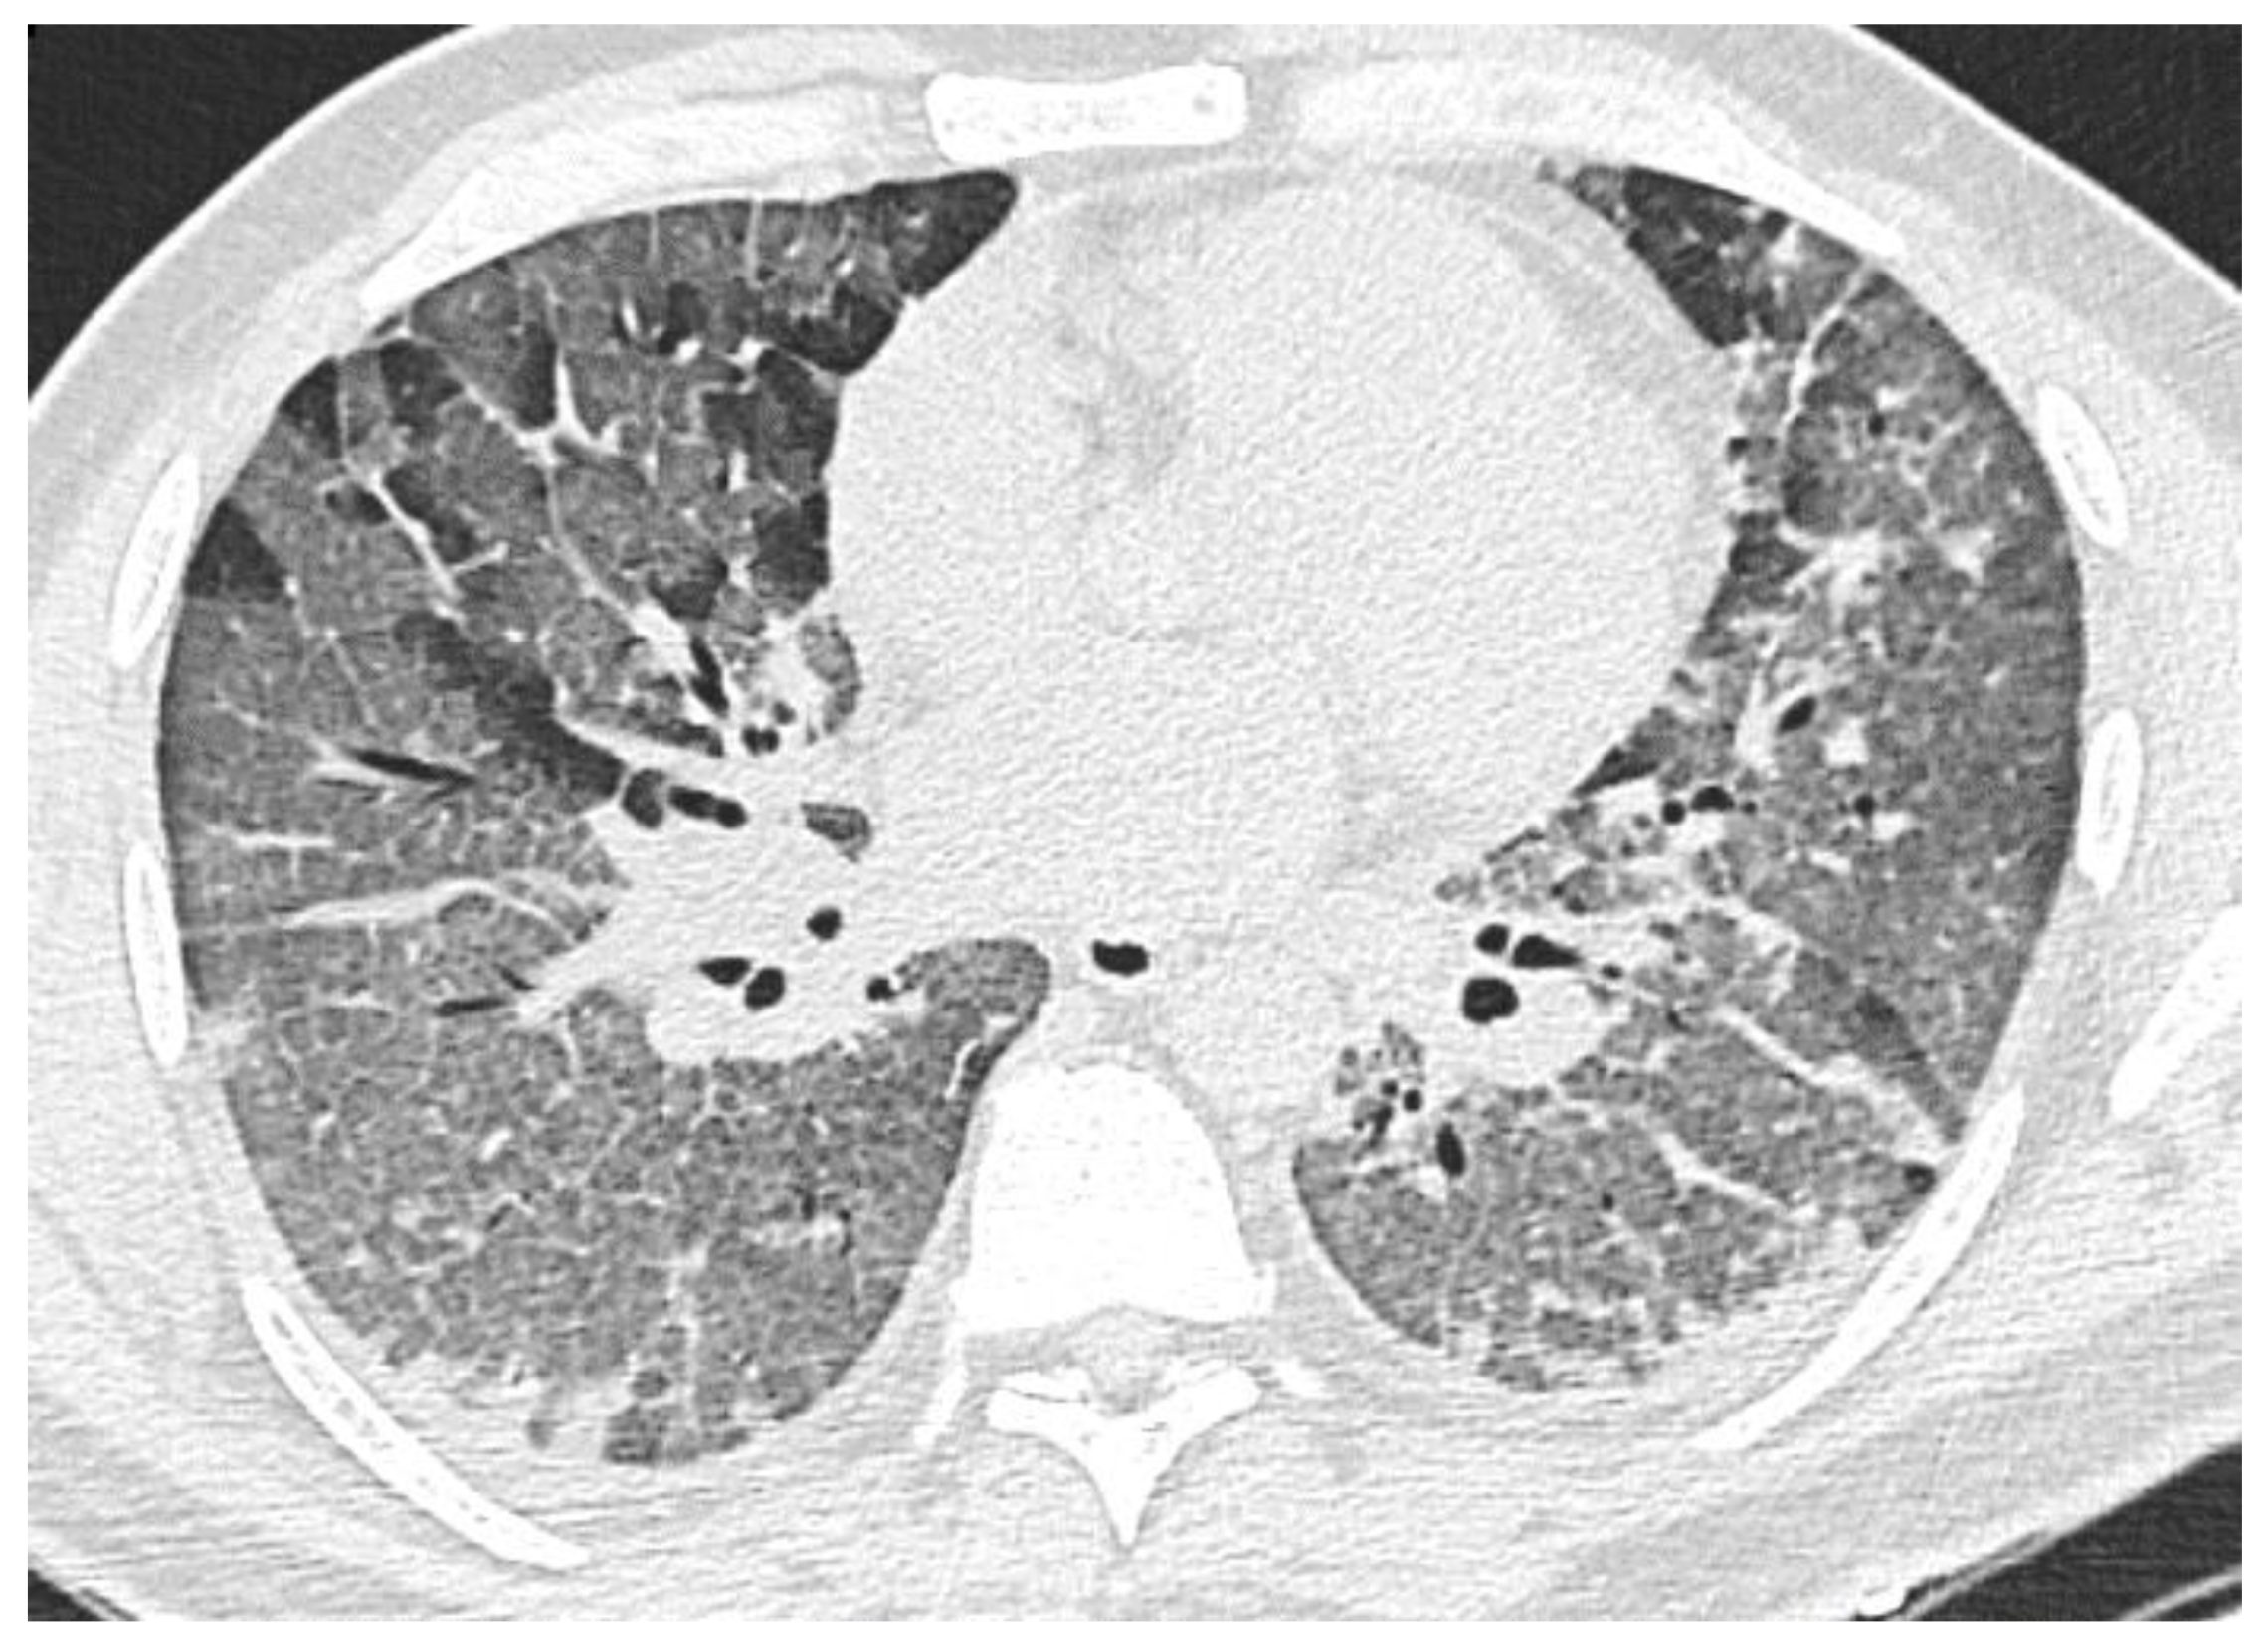

3.2.3. “Crazy Paving” Pattern

3.2.4. Reticular Interstitial Pattern, Pleuroparenchymal Bands

- Peak (9–13 days): predominance of a combination of GGO (87%), consolidations (67%), and RC (54%) in recovered patients and the combination of CP (87%), consolidations (77%) and RC (65%)—in deceased. RC demonstrated ascending trend in both cohorts, consolidations—in recovered patients, CP—in deceased, the contribution of GGO decreased in both;